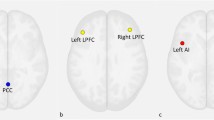

Adults with psychotic disorders have dysconnectivity in critical brain networks, including the default mode (DM) and the cingulo-opercular (CO) networks. However, it is unknown whether such deficits are present in youth with less severe symptoms. We conducted a multivariate connectome-wide association study examining dysconnectivity with resting state functional magnetic resonance imaging in a population-based cohort of 188 youths aged 8–22 years with psychosis-spectrum (PS) symptoms and 204 typically developing (TD) comparators. We found evidence for multi-focal dysconnectivity in PS youths, implicating the bilateral anterior cingulate, frontal pole, medial temporal lobe, opercular cortex and right orbitofrontal cortex. Follow-up seed-based and network-level analyses demonstrated that these results were driven by hyper-connectivity among DM regions and diminished connectivity among CO regions, as well as diminished coupling between frontal and DM regions. Collectively, these results provide novel evidence for functional dysconnectivity in PS youths, which show marked correspondence to abnormalities reported in adults with established psychotic disorders.